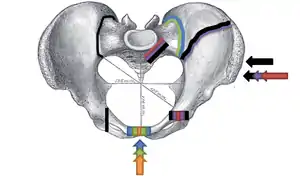

Pelvic fracture

Pelvic vertical shear fracture

Fractures of the superior (in two places) and inferior pubic rami on the person's right, in a person who has had prior hip replacements

Classification

Pelvic fractures are most commonly described using one of two classification systems. The different forces on the pelvis result in different fractures. Sometimes they are determined based on stability or instability.[8]

The Young-Burgess classification system is based on mechanism of injury: anteroposterior compression type I, II and III, lateral compression types I, II and III, and vertical shear,[5] or a combination of forces.

The most common force type, lateral compression (LC) forces, from side-impact automobile accidents and pedestrian injuries, can result in an internal rotation.[9] The superior and inferior pubic rami may fracture anteriorly, for example. Injuries from shear forces, like falls from above, can result in disruption of ligaments or bones. When multiple forces occur, it is called combined mechanical injury (CMI). The best imaging modality to use for this classification is probably a pelvic CT scan.

Open book fracture

One specific kind of pelvic fracture is known as an 'open book' fracture. This is often the result from a heavy impact to the groin (pubis), a common motorcycling accident injury. In this kind of injury, the left and right halves of the pelvis are separated at front and rear, the front opening more than the rear, i.e. like an open book that falls to the ground and splits in the middle. Depending on the severity, this may require surgical reconstruction before rehabilitation.[10] Forces from an anterior or posterior direction, like head-on car accidents, usually cause external rotation of the hemipelvis, an “open-book” injury. Open fractures have increased risk of infection and hemorrhaging from vessel injury, leading to higher mortality.[11]